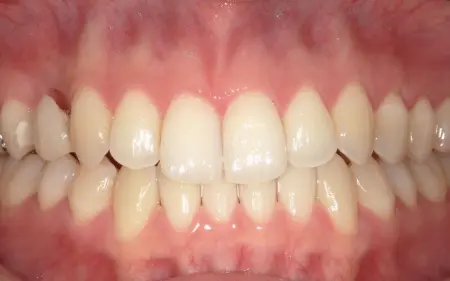

2025.12.2710代女性 突出感のある口元と乱れた歯並びをワイヤー矯正で改善した症例